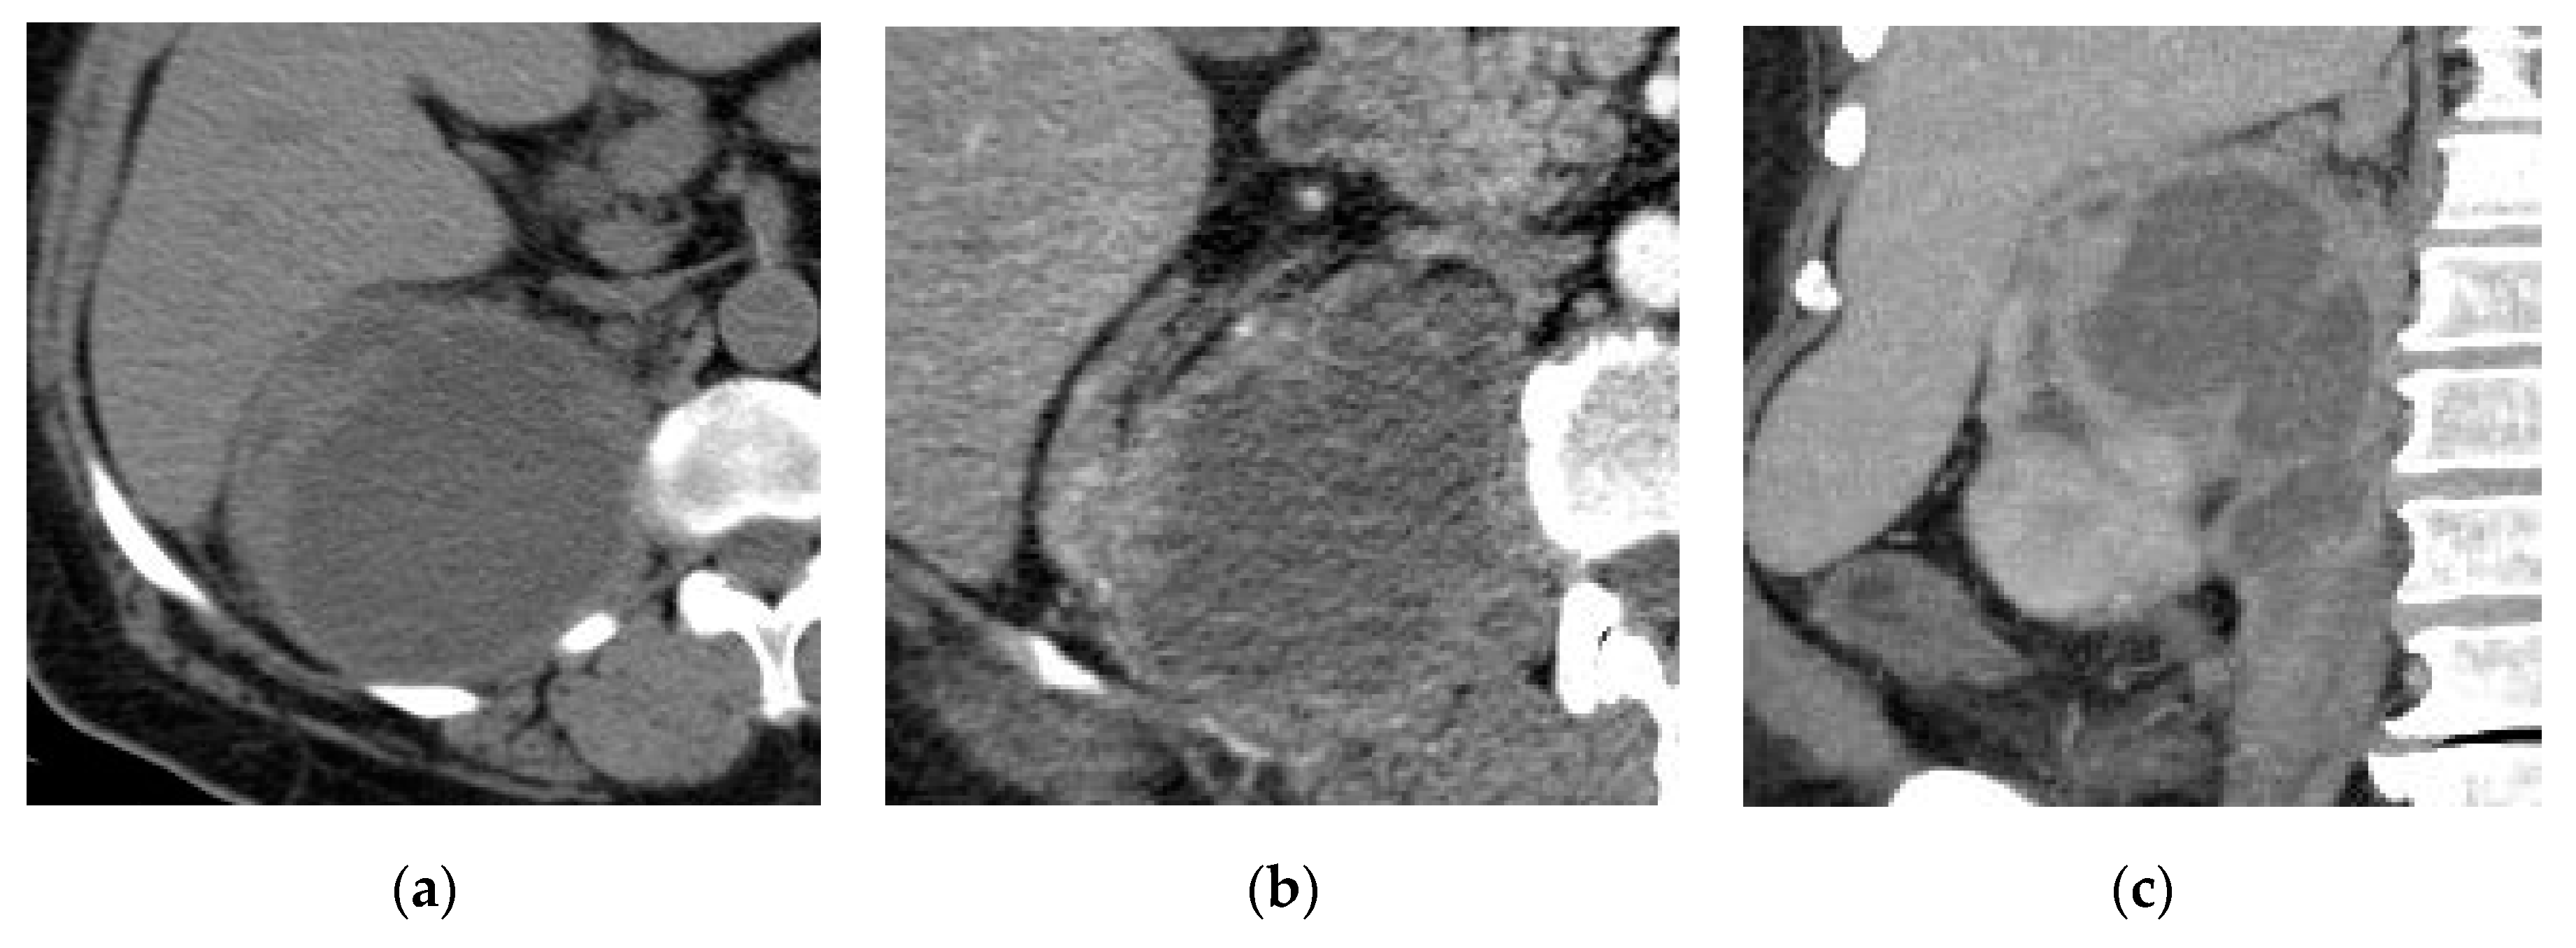

2.1. Acute Pyelonephritis

| Acute pyelonephritis | Wedge shaped hypo-enhancing areas or striated nephrogram pattern. Perinephric fat stranding and thickening of Gerota’s fascia. |